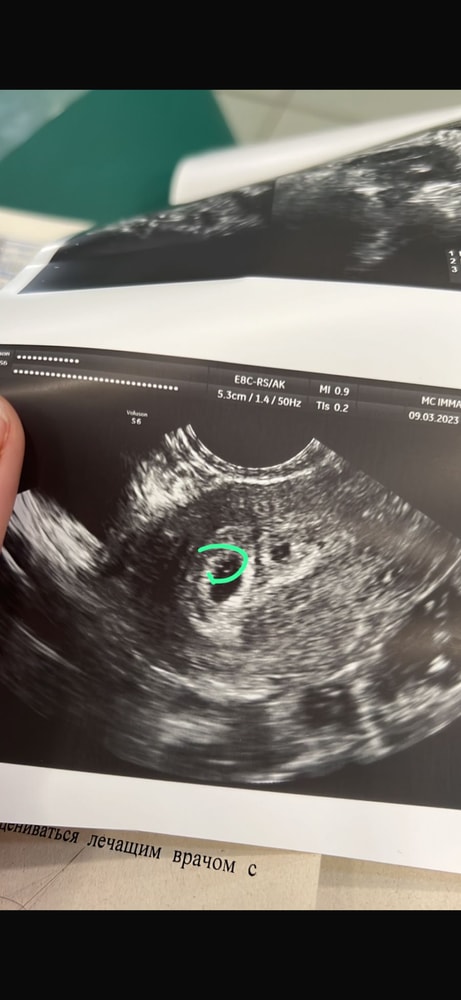

Вчера была на узи - нашла ПЯ 3 мм, совсем мелкое, но я то думала, что ХГЧ хорошо растет и ожидала ПЯ побольше, а ХГЧ там тормознулся видимо. По месячным 5+3 нед. Это все? Такая динамика не сулит ничего успешного?

Наталья, я ходила в платные хорошие клиники. Вот вам для примера два узи, на обоих дала 9/03. На первом сказали яйца пустые, на втором узи врач уже видела мешочек. Второй ПЯ у меня был поменьше, но тоже развился эмбрион и все хорошо